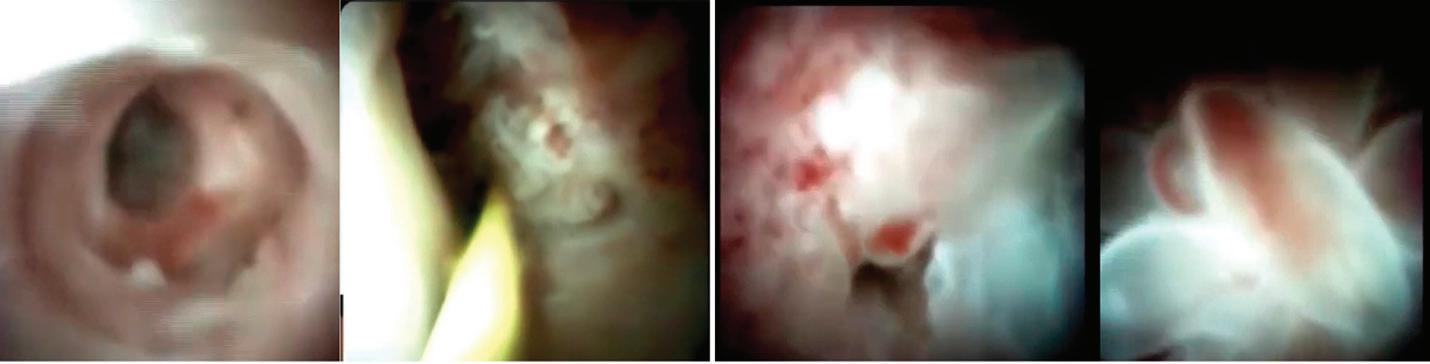

Постъпва в увредено общо състояние, афебрилна. Леко изразен периорбитален оток. Генералициран макуло-папулозен обрив по

При около 10% от случаите на инфекциозна мононуклеоза се развива кожен обрив. Той е макулопапулозен,

обикновено несърбящ екзантем, за който се смята, че е пряко свързан с вируса. Появява се първо по торса, горната част на ръцете и по-късно се разпространява по лицето. Този обрив е различен от обрива, който възниква при употребата на бета-лактамни и други антибиотицисърбящ, морбилиформен обрив[5].

1. Първи ден на хоспитализация 2. Трети ден при повишаване на температура